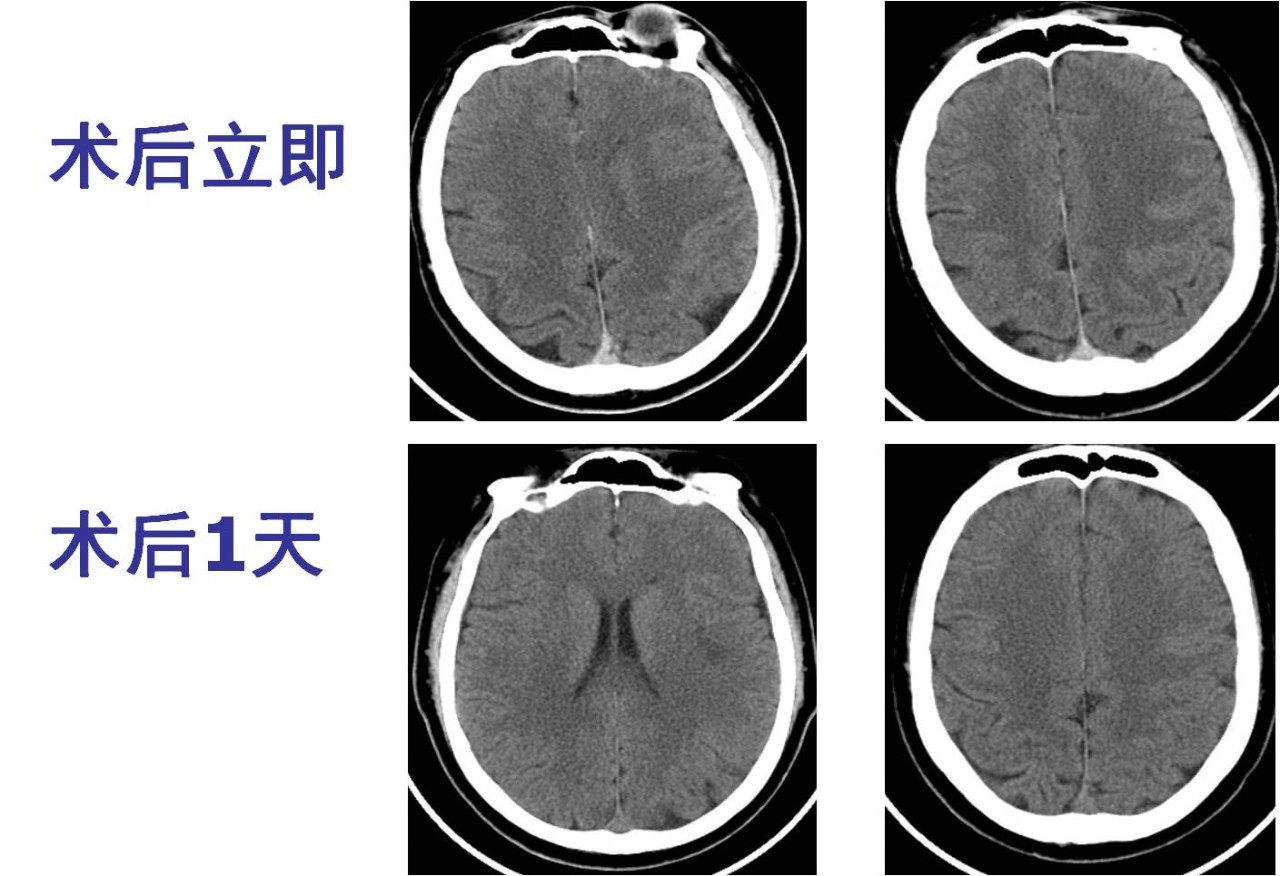

术后管理

》术后监测生命体征;

》复查头颅CT了解有无脑出血等并发症 ;

术后情况

》呼吸平稳,口腔分泌物减少,吞咽功能改善。

》能简单回答问题,左侧肢体肌力4级。

>>术后1天